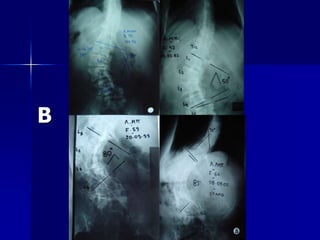

2ος Τύπος Εξέλιξη της

εφηβικής ιδιοπαθούς σκολίωσης στους ενήλικες. Ascani E, et al, 1986 Aebi M. , 2005 A

B